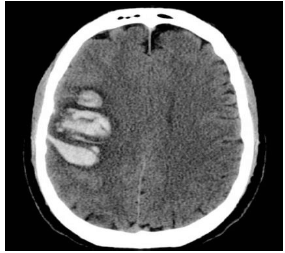

Paciente de 65 anos, do sexo masculino, com antecedente de hipertensão arterial mal controlada e diabetes, é admitido na UTI com o diagnóstico de acidente vascular cerebral hemorrágico de etiologia hipertensiva.

Ao ser admitido, apresenta-se em Glasgow 15, hemiplégico à direita, disártrico e com paralisia facial de padrão central, sem outras alterações ao exame neurológico. Encontra-se ainda com FC 65, PA 190x110, FR 18, SatO2 97% em ar ambiente e com glicemia capilar de 350mg/dL.

A imagem a seguir ilustra uma tomografia de crânio realizada no Pronto Socorro.

Enunciado 3137177-1

Na prescrição deste paciente da UTI devem constar os seguintes itens, à exceção de um. Assinale-o.